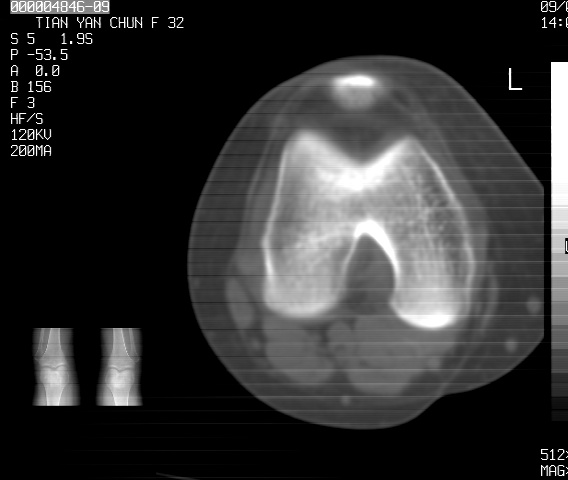

标题: CT18487:请会诊,女32岁,左膝疼痛数日 [打印本页]

标题: CT18487:请会诊,女32岁,左膝疼痛数日

关节面软骨有硬化环考虑退行性变

定位片可见髁间棘骨质增生,支持膝关节退行性变。

定位片可见髁间棘骨质增生,支持膝关节退行性变。建议mri 检查

考虑骨性关节炎